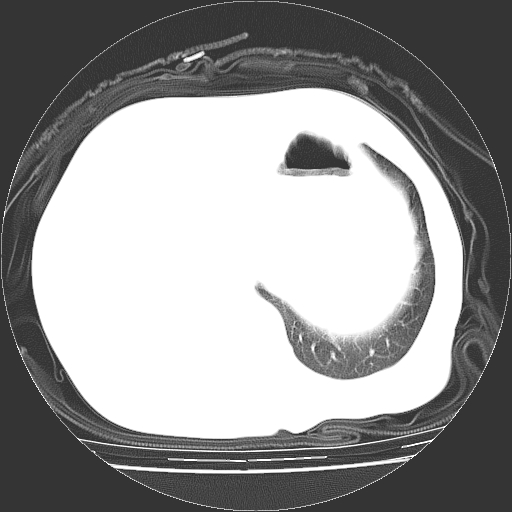

标题: CT23991:女,72岁,咳嗽、憋气一周。 [打印本页]

女,72岁,咳嗽、憋气一周,十年前曾患肺结核及胸膜结核。

右侧毁损肺,右侧纵隔疝

右侧毁损肺,右侧纵隔疝,左肺代偿!

1.右侧损毁肺伴胸膜钙化,2.左肺小结节灶,良性可能大,注意复查。3.肝脏左叶囊肿。4.先天性一侧肺不发育待出外(右侧胸廓无明显塌陷)。对比原片应该非常有帮助。